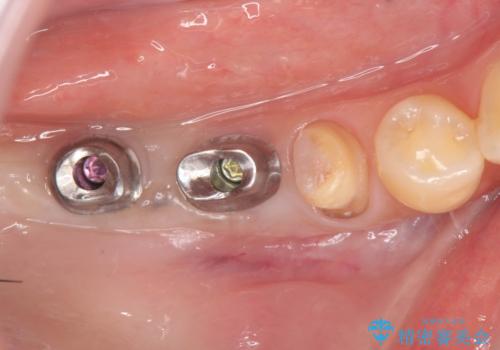

- 176万円(インプラント×4・チタンカスタムアバットメント×4・ジルコニアクラウン×4・仮歯×4)費用は治療当時の料金となります

- 外科手術のため、術後に痛みや腫れ、違和感を伴います

- メンテナンスを怠ったり喫煙により、お口の中に大きな悪影響を及ぼすインプラント周囲炎等にかかる可能性があります

- 糖尿病、肝硬変、心臓病等の場合、インプラント治療ができない可能性があります

- 高血圧、貧血・不整脈等の場合、インプラント治療後に治癒不全を招く可能性があります